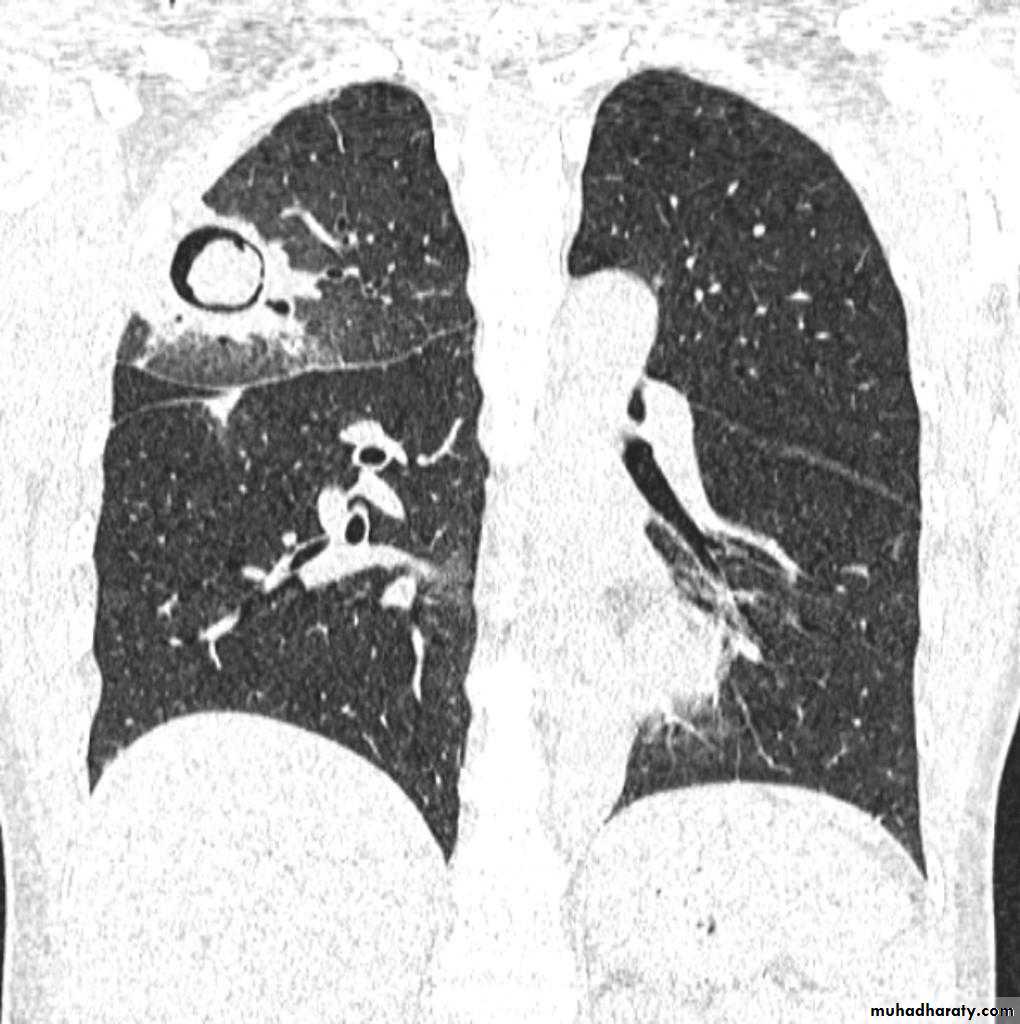

The appearance depends on the location of the lesion.

1.The more central lesions may merely appear as a bulky hilum, representing the tumor and local nodal involvement the lesion is irregular in outline have spiky or sun ray spiculation .

2.Lobar collapse may be seen due to obstruction of a bronchus. When the right upper lobe is collapsed and a hilar mass is present, this is known as the Golden S sign.

3.A more peripheral location may appear as a rounded or spiculated mass. Cavitation may be seen as an air-fluid level , more to be large cell CA .